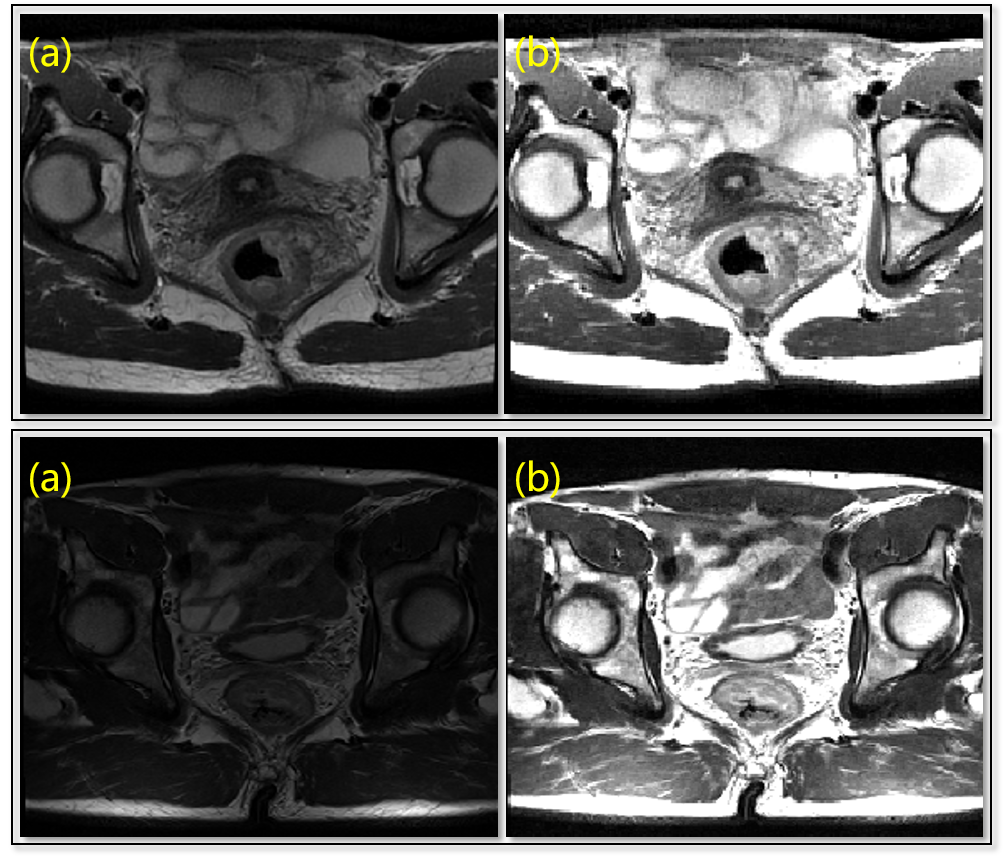

Different spacing rates are normalized to as the HighRes set. Some part-based methods listed in TABLE 2 employ down-sampled image sets, namely LowRes set of mm spacing and MidRes set of spacing. To normalize the intensities of input images acquired under different imaging configurations and field of views, we perform in-body intensity normalization to exclude the affect of inconsistent body-to-background ratios. By OTSU[54] thresholding, connectivity analysis and closing operation, body masks are extracted as foreground and other voxels are set as background. The mean intensity and standard deviation are computed within the body mask according to following formulas:

A few examples of the comparison between original images and intensity-normalized images are illustrated in Fig. 4.